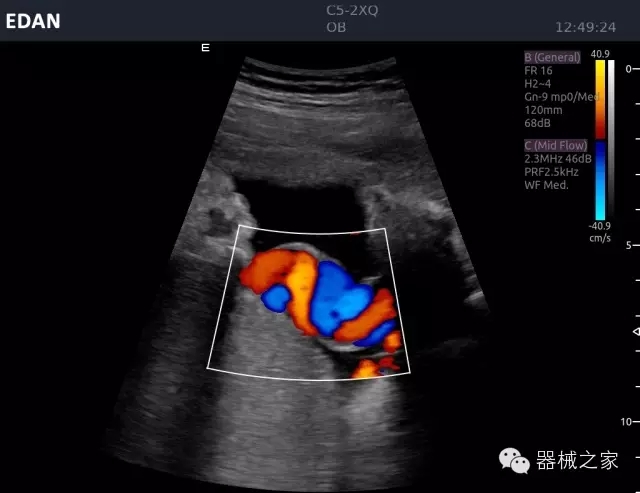

睪丸低速血流